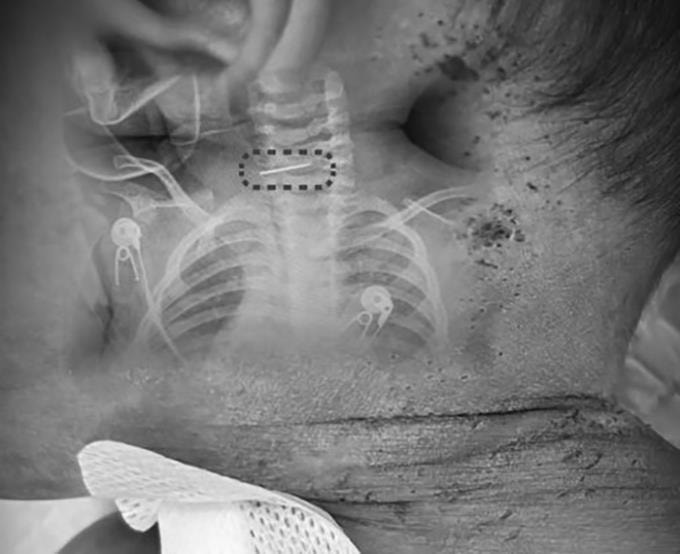

Bé trai 10 tháng tuổi tại tỉnh Vân Nam nhập viện với khoảng 600 vết kim châm khắp người do mẹ ruột tin vào phương pháp "chích máu" dân gian mỗi khi con quấy khóc.

Bé trai 10 tháng tuổi có nhiều vết kim đâm khắp cơ thể. Ảnh: Red Star News

Trước đó, bác sĩ Tùy Văn Nguyên (Sui Wenyuan), Trung tâm Cột sống thuộc Bệnh viện Tân Hoa (Đại học Y khoa Giao thông Thượng Hải), tiếp nhận bệnh nhi trong tình trạng sốt cao. Kết quả kiểm tra cho thấy cơ thể bé, từ đầu, thân đến tứ chi, chi chít khoảng 500 đến 600 vết kim đâm đã đóng vảy đen.

Nghiêm trọng nhất, bác sĩ phát hiện một cây kim khâu giày gãy đôi, mắc kẹt sâu trong đốt sống cổ của bệnh nhi. Êkíp lập tức tiến hành phẫu thuật khẩn cấp để lấy dị vật. Theo bác sĩ Tùy, đây là ca mổ cực kỳ phức tạp bởi cột sống cổ của trẻ 10 tháng tuổi chưa hoàn thiện, cấu trúc lỏng lẻo khiến rủi ro cao gấp nhiều lần người lớn.